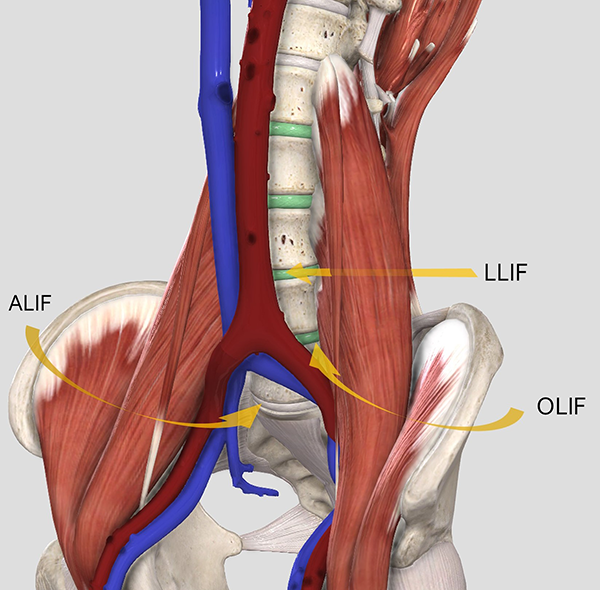

Figura 1: Representación esquemática de los abordajes anterolaterales al disco intervertebral. ALIF, fusión lumbar intersomática anterior; OLIF, fusión lumbar intersomática oblicua; LLIF, fusión lumbar intersomática lateral.

Existen múltiples vías de abordaje para acceder al espacio discal y realizar una LIF. Las técnicas por vía posterior incluyen la fusión intersomática posterior (PLIF), transforaminal (TLIF) y extra foraminal (ELIF).1 Las técnicas anterolaterales (Figura 1) incluyen la fusión lumbar intersomática anterior (ALIF, por sus siglas en inglés) y la vía lateral transpsoas (LLIF, por sus siglas en ingles). Si bien estas últimas técnicas han sido descriptas en forma reciente, han ganado cada vez más importancia en el arsenal terapéutico del cirujano de columna.2,3

Figura 1: Representación esquemática de los abordajes anterolaterales al disco intervertebral. ALIF, fusión lumbar intersomática anterior; OLIF, fusión lumbar intersomática oblicua; LLIF, fusión lumbar intersomática lateral.